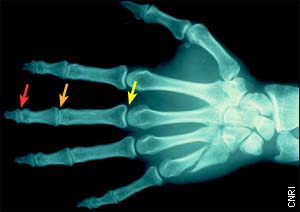

The red arrow denotes the distal interphalangeal (DIP) joint; the orange arrow, the proximal interphalangeal (PIP) joint; and the yellow arrow, the metacarpophalangeal (MCP) joint. Side note: this X-ray image shows a fractured metacarpal bone (below the little finger).

Dr. Scott: Each finger has three bones -- the distal (fingertip), middle, and proximal phalanges -- and, like other joint structures in the body, it's stabilized by ligaments and tendons. When the finger receives a blow to the tip, the ligaments and tendons can be stretched and torn, and one or more of three joints can be injured: the distal interphalangeal (or DIP; the first knuckle), proximal interphalangeal (or PIP; the middle knuckle), and metacarpophalangeal (MCP; the knuckle at the base of the finger).